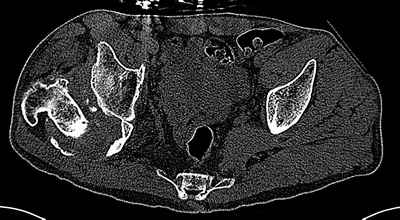

Уважаемые коллеги. Пациент 30 лет 3 года назад в результате травмы получил травматический дефект нижних конечностей до в/3 голеней, был пропущен вывих бедра.

На последнем срезе КТ задний край практически отсутсвует по сравнения со здоровой стороной. Разумеется, что это плоскостное изображение, но головка вывихнулась не только в плоскостную щель захваченную на КТ. Если вы считаете, что удастся установить туда чашку даже низкопрофильную, остается пожелать вам успехов. Но перед этим можно смоделировать установку чашки на скиаграммах КТ.

За пожелание успехов - спасибо, думаю это пригодится, не очень понял про плоскостную щель, специально предоставил срезы на уровне свода - он цел, дефект заднего края ниже, за счет заглубления он будет еще меньше, по данным 3d - должно получиться.